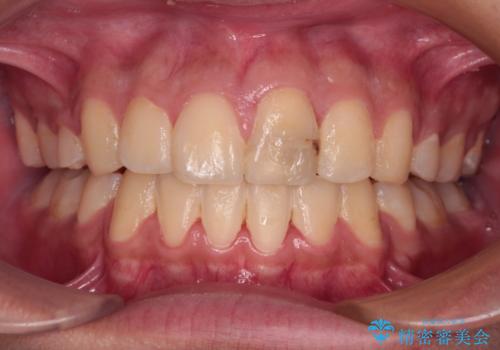

- 咬み合わせが悪いとのことで来院された患者様です。

ぱっと見はインビザラインによる矯正治療も可能と思われましたが、歯根が最も長い犬歯がクロスバイトになっており、インビザラインでは対応困難と判断され、ワイヤー装置にて矯正治療を行うこととしました。

クロスバイトになっている犬歯は、歯の移動に伴い装置を張り替えていくことで対応することとしました。